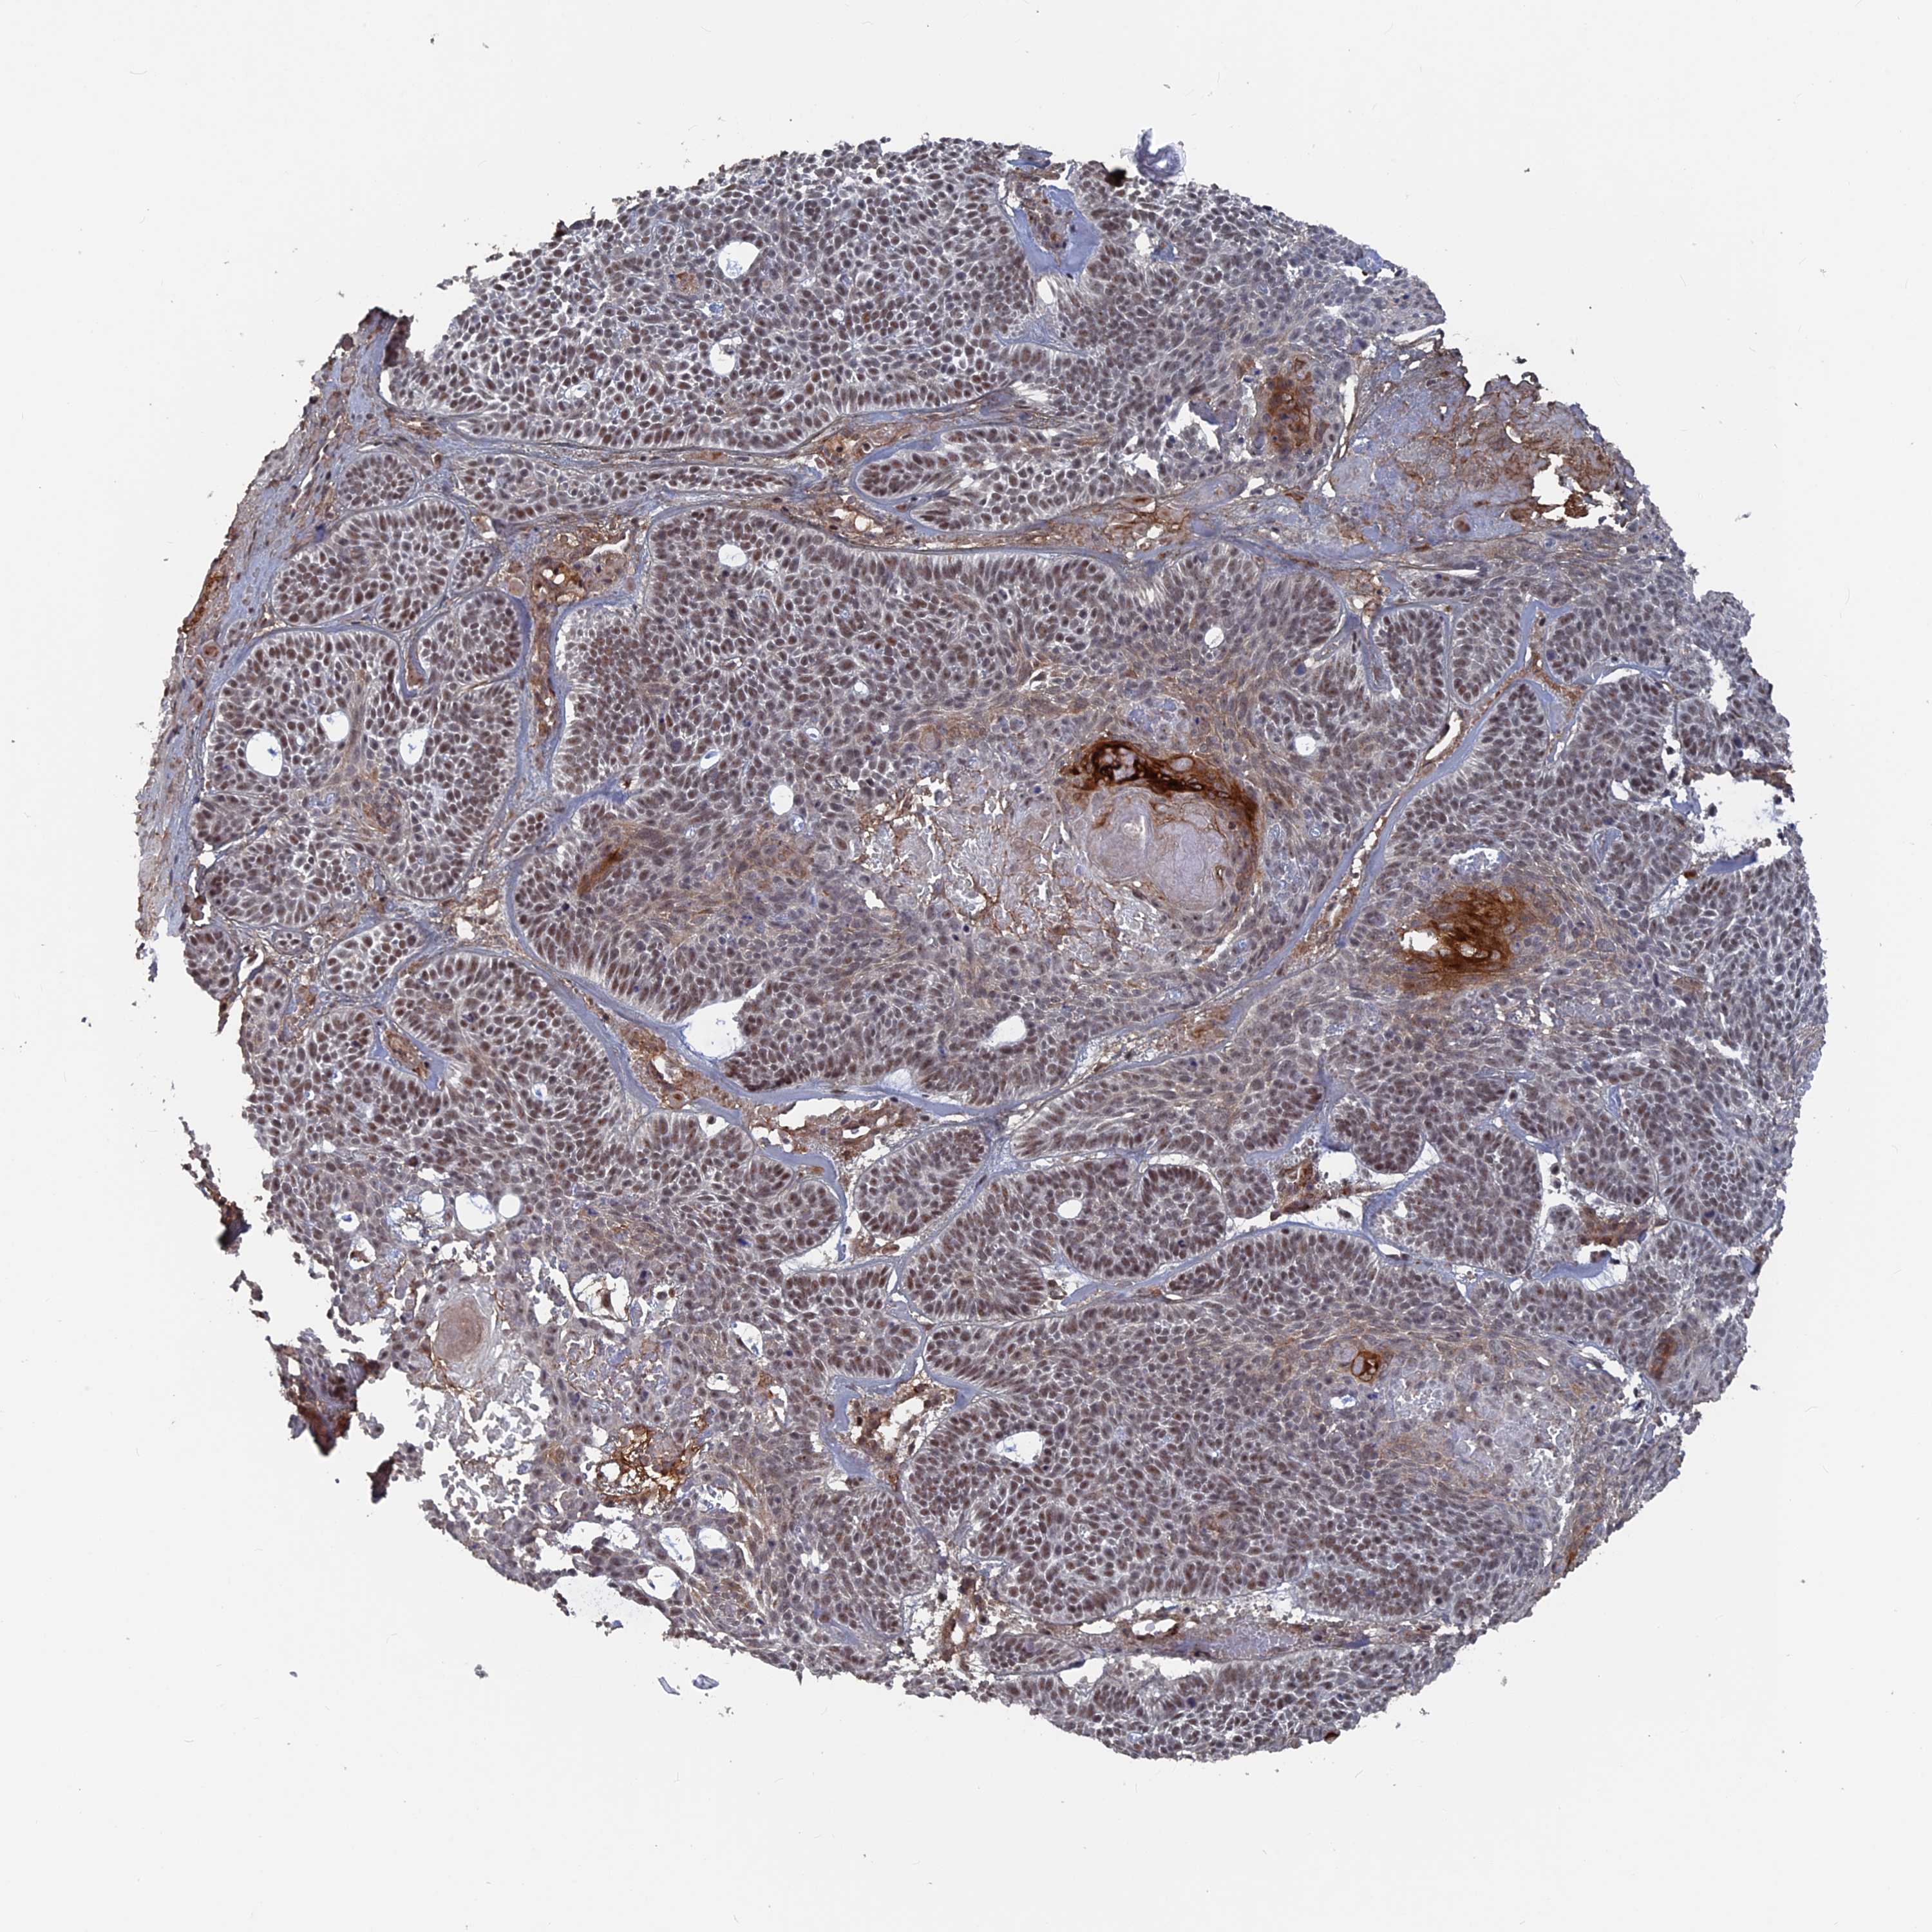

SKIN CANCER - Protein expressioni

A mouse-over function shows sample information and annotation data. Click on an image to view it in a full screen mode. Samples can be filtered based on level of antibody staining by selecting one or several of the following categories: high, medium, low and not detected. The assay and annotation is described here.

Antibody stainingi

Antibody staining in the annotated cell types in the current human tissue is reported as not detected, low, medium, or high, based on conventional immunohistochemistry profiling in selected tissues. This score is based on the combination of the staining intensity and fraction of stained cells.

Each image is clickable and will lead to virtual microscopy that enables deeper exploration of all samples and also displays staining intensity scores, fraction scores and subcellular localization as well as patient and tissue information for each sample.

Antibody HPA042212

Basal cell carcinoma

Squamous cell carcinoma, NOS

Squamous cell carcinoma, metastatic, NOS